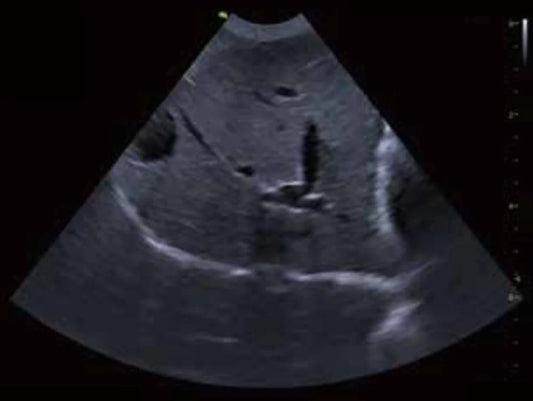

Exploración Abdominal en Veterinaria: Clave par...

La ecografía abdominal es una herramienta fundamental en la medicina veterinaria moderna, ya que permite visualizar en tiempo real los órganos internos de los animales sin procedimientos invasivos. A través...